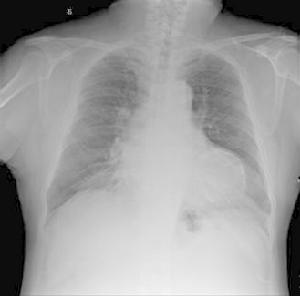

2.肺臟 在感染、創傷或手術後出現低氧血症,進一步發展以呼吸困難為特徵的成人呼吸窘迫綜合徵(ARDS)。呼吸頻率>28 次/min,PaO2 進行性下降,PaO2<8.00kPa 時病人發生高碳酸血症;PaCO2>6.67kPa 時病人需吸氧(FiO2>50%)。A-aDO2>46.6kPa。根據老年人的具體情況,有呼吸窘迫,並使用了呼吸機,診斷即可成立。

5.其他輔助檢查:肺部感染者,X 線可顯示異常。